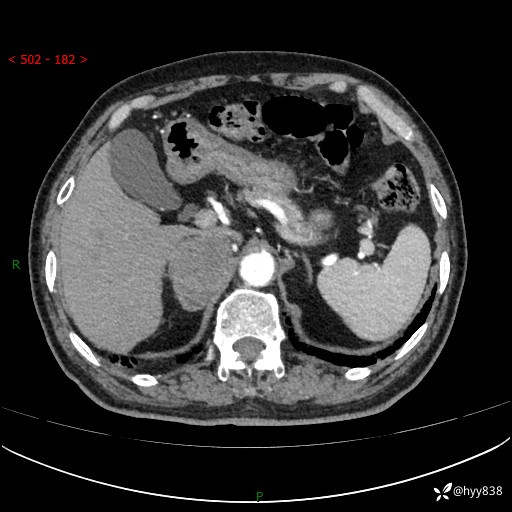

【患者信息】:76岁/男

【主诉】:检查发现右侧肾上腺占位6天

【现病史及既往史】:患者6天前体检发现右侧肾上腺占位,无腰痛,无放射痛,无尿频、尿急、尿痛及肉眼血尿,无畏寒、发热,无恶心、呕吐,今为求进一步治疗,遂来我院就诊,门诊拟“右侧肾上腺占位”收住入院。 起病以来,患者精神、饮食、睡眠可,大小便如常,体力体重无明显变化。

【检查】:肾上腺CT平扫+增强